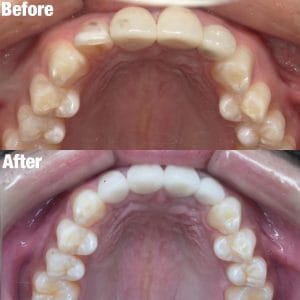

Case025

他院ですでに3本セラミック治療を行っている男性の患者様です。

歯並びと色を変えたいということで当院にお越しくださいました。

・透明感のあるセラミックに変更

・前に出ている歯を内側に入れてスマートな印象に

したことにより、とても洗練された口元になったと思います。

この白い色もとてもお似合いの方で、治した私もセット後に思わず「似合いますね」と言ってしまいました。

当院はセラミック矯正だけではなく、マウスピース矯正、ワイヤー矯正と全ての治療メニューを用意しております。

患者様の主訴と悩み、治療費にかけられる費用と期間をお伺いし、ご要望に合う治療方針をご提案、ご相談しながら決めています。

この方の場合は

・既に歯を3本削られている

・前医で入れた大きなセラミックは矯正しても小さくはならない

・色を変えたい

以上の理由でセラミック矯正を選んでおります。